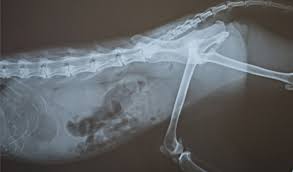

Colon Cancer Symptoms In Dogs from 1.bp.blogspot.com The dog's weight, temperature, pulse and blood pressure will be taken. Don't be afraid to call your vet and ask for advice, a quick opinion or for your pet to be seen. In dogs the most common sites for instestinal tumors are the colon and the rectum. Ibd is often referred to as a primary inflammatory diseases, because it. Two types of colon cancer exist in dogs: Sometimes a veterinarian will proclaim cancer but has not collected a specimen for analysis. Less often, part of the colon may need to be surgically removed to make the diagnosis. Changes in body weight, appetite and vitality are potential signs of cancer of the colon in your pet.

Your veterinarian will perform a complete physical examination on your dog, with blood tests, fecal tests and a biochemistry profile. Two types of colon cancer exist in dogs: Diarrhea, constipation, and vomiting also show anything will go incorrect with your pet's digestive tract. Symptoms include a mass on the gums, bleeding, odor, or difficulty eating. Usually if a suspected colorectal cancer is found by any screening or diagnostic test, it is biopsied during a colonoscopy. They may strain to defecate and go more often than normal. The best thing for you to do is giving your pet comes to the veterinary clinic to be diagnosed correctly by the doctor. This can happen when there is a high suspicion of cancer, for example, an enlarged spleen in a dog who is not acting right. Clinical diagnosis if your vet believes colon cancer may be the root of your pet's health issues, he will conduct a physical exam and laboratory tests to reach a definitive diagnosis. Clinical signs of intestinal cancer are weight loss, loss of appetite, vomiting, diarrhea and blood in vomit or feces. the usual clinical signs of intestinal cancer are weight loss, loss of appetite, vomiting, diarrhea and blood in vomit or feces. Symptoms of dogs with cancer. Lymphoma/lymphosarcoma is diagnosed when the lymph nodes or lymphoid tissues in the gastrointestinal tract are affected. If your dog collapses, get to the vet immediately.

They may strain to defecate and go more often than normal. Usually if a suspected colorectal cancer is found by any screening or diagnostic test, it is biopsied during a colonoscopy. Manual palpation or probing of the stomach is a common first step, followed by a rectal examination. On the other hand, leimyosarcomas and gastrointestinal stromal tumors normally originate in the cecum (first part of the small intestine). And, in fact, from dog skin cancer to breast cancer, cancer in dogs varies just as it does in people.but knowing some of the common signs of cancer in dogs may just save their life. If the dog is overly stressed and/or scared, the veterinarian may suggest using a muzzle. Two types of colon cancer exist in dogs: While many of the following symptoms may be indicative of less serious. Clinical diagnosis if your vet believes colon cancer may be the root of your pet's health issues, he will conduct a physical exam and laboratory tests to reach a definitive diagnosis. The patient will then have a physical exam. Don't be afraid to call your vet and ask for advice, a quick opinion or for your pet to be seen. Samples include tissue, fluids, or cells. A lump or a bump, a wound that doesn't heal, any kind of swelling, enlarged lymph nodes, a lameness or swelling in the.

9z Mbefzdngjem from images.saymedia-content.com Diagnosis you will need to provide a thorough history of your dog's health leading up to the onset of symptoms. Intestinal tumors are uncommon in dogs and cats. Diarrhea, constipation, and vomiting also show anything will go incorrect with your pet's digestive tract. There are many types of cancers that. In order to formally diagnose or rule out colon cancer in your dog, your vet will need to perform a range of tests as well as taking into account your dog's history, and a thorough physical examination. Possible symptoms of adenocarcinomas include weight loss, diarrhea, and loss of appetite. The dog's weight, temperature, pulse and blood pressure will be taken. Doctors recommend certain screening tests for healthy people with no signs or symptoms in order to look for signs of colon cancer or noncancerous colon polyps.

These are normally reviewed to see if there are cancer cells in the sample. Two types of colon cancer exist in dogs: In order to formally diagnose or rule out colon cancer in your dog, your vet will need to perform a range of tests as well as taking into account your dog's history, and a thorough physical examination. Adenosarcoma is diagnosed when the tumor(s) grow from the apocrine glands located on each side of the rectum. Doctors recommend certain screening tests for healthy people with no signs or symptoms in order to look for signs of colon cancer or noncancerous colon polyps. Lymphoma/lymphosarcoma is diagnosed when the lymph nodes or lymphoid tissues in the gastrointestinal tract are affected. The patient will then have a physical exam. Clinical diagnosis if your vet believes colon cancer may be the root of your pet's health issues, he will conduct a physical exam and laboratory tests to reach a definitive diagnosis. What are the different types of imaging techniques used to diagnose cancer in cats and dogs? Screening has been shown to reduce your risk of dying of colon. Less often, part of the colon may need to be surgically removed to make the diagnosis. While many of the following symptoms may be indicative of less serious. Most intestinal tumors are malignant.